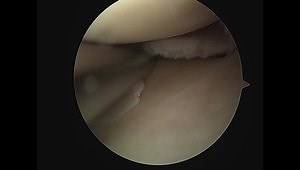

Medial Meniscus Tear - MRI Knee Meniscus